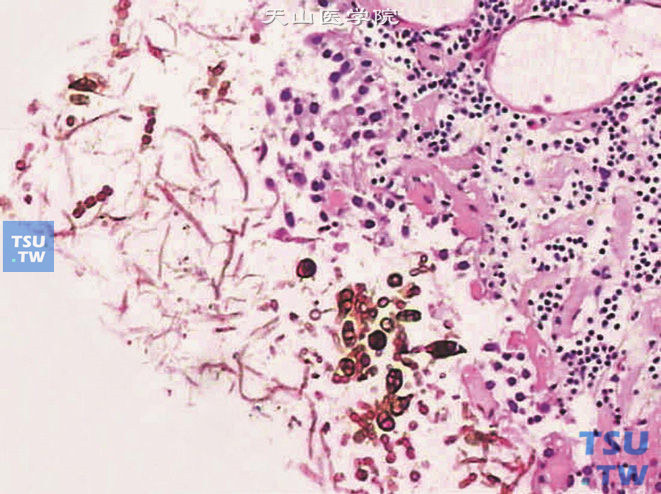

• 真菌性膀胱炎病理图谱

上图:真菌性膀胱炎,放线菌脓肿上图:真菌性膀胱炎,可见孢子和假菌丝上图:真菌性膀胱炎,上图高倍,示孢子和菌丝